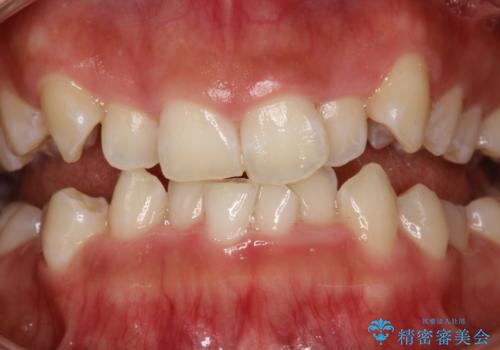

- 矯正治療前にステインを取りたいとのことで来院されました。ステインは前歯のみだったため、PMTC30分コースを行いました。

PMTCとは、歯科の専門家が器械を使用して行う歯のクリーニングのことです。普段の歯磨きでは取り切れない溝、キワなどの細かい部分も徹底的に除去します。ステインや歯石などが付着したままだと、虫歯や歯周病の発見がしずらいことがあります。特に矯正治療前には、念入りな虫歯や歯周病チェックが必要なため、PMTCでしっかりと汚れを除去しておくことが大切です。